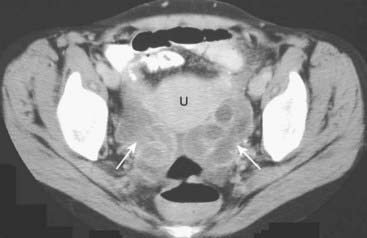

image

Figure 19-22 Pelvic inflammatory disease, sagittal and transverse views, US.

A, A fluid-filled and dilated fallopian tube (FT) containing pus and debris (solid black arrow) representing a pyosalpinx is demonstrated. B, Due to progressive inflammation, there is fusion of a dilated and tortuous fallopian tube (solid black arrow, FT) and the adjacent ovary (solid white arrow, OV) producing a tubo-ovarian complex.

Figure 19-23 Bilateral pyosalpinges in pelvic inflammatory disease, CT.

There are dilated, serpiginous, and fluid-filled tubular structures bilaterally (solid white arrows) representing pyosalpingitis of both fallopian tubes on this scan of the pelvis in a young female with pelvic inflammatory disease. (U = uterus.)